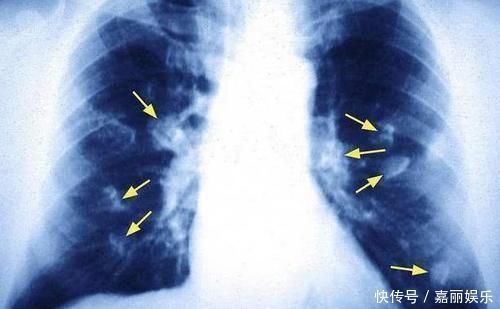

文章插图